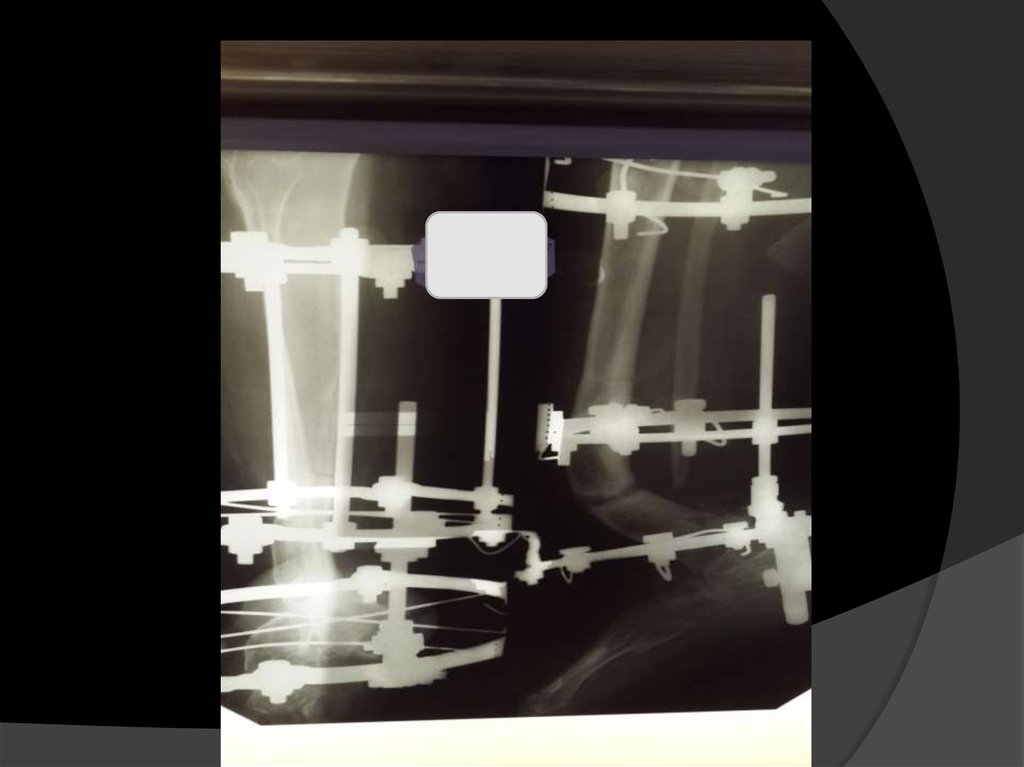

Лечение варусно-рекурвационной деформации в нижней трети правой голени аппаратом Илизарова вследствие родовой травмы

Больная Б 22г поступила в отделение с

диагнозом:Сложная многокомпонентная

варусно-рекурвационная деформация н\3

правой голени вследствии родовой

травмы. Дисплазия правой малоберцовой

кости в н\3,правой стопы.Атрофический

псевдоартроз н\3 б\берцовой кости.

Кратко ход операции: на среднюю и н\3 правой голени

наложено базовое и проксимальное репонирующее кольцо.

В области н\3 правой голени дистальное репонирующее

кольцо фиксированное перекрестно двумя спицами и

дополнительно на выносных проведена спица через

таранную кость. Репонирующие кольца связаны четырьмя

двухосевыми шарнирами на уровне деформации.

Работа с аппаратом:компрессия передних

шарниров 1,5мм в сутки, дистракция задних

1,5мм в сутки.

Рентген контроль в сентябре 15г.